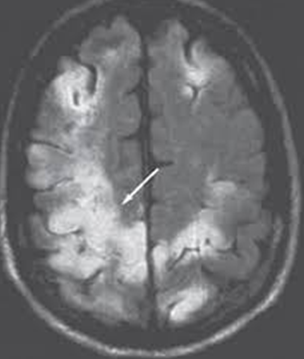

Ensefalit tanısının konmasında en önemli basamak hastanın şikayetlerinin ve nörolojik bulgularının değerlendirilmesidir. Bunu beyin görüntülemesi, tercihen ilaçlı beyin MR’ı izler. Sıklıkla kesin tanı için de beyin omurilik sıvısının (bel suyu incelemesi de gereklidir.